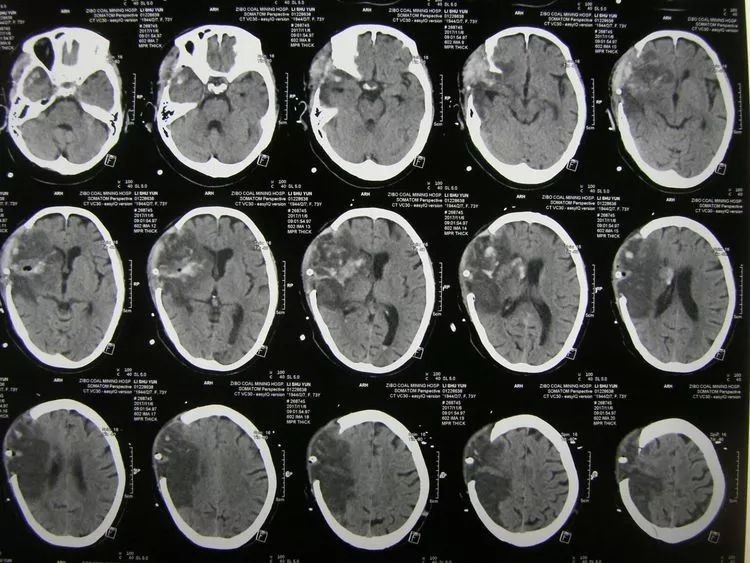

I am not detecting a great deal of pride in workmanship. Another example? Fig 1 of Xie et al (2021), “Chronic obstructive lung characteristics”, turns out to be sourced from “Case 28-2019: A 22-Year-Old Woman with Dyspnea and Chest Pain“… though filtered through a series of Chinese websites. While on close inspection of Fig 6, “The current quality of life of COPD patients at different stages of pulmonary rehabilitation exercise behavior”, the panels turn out to be not directly lung-related, but MRI-scan slices of a massive cerebral hemorrhage. Happily, the 73-year-old patient was saved by prompt craniectomy and decompression. The putative authors do warn us that “No data were used to support this study”.